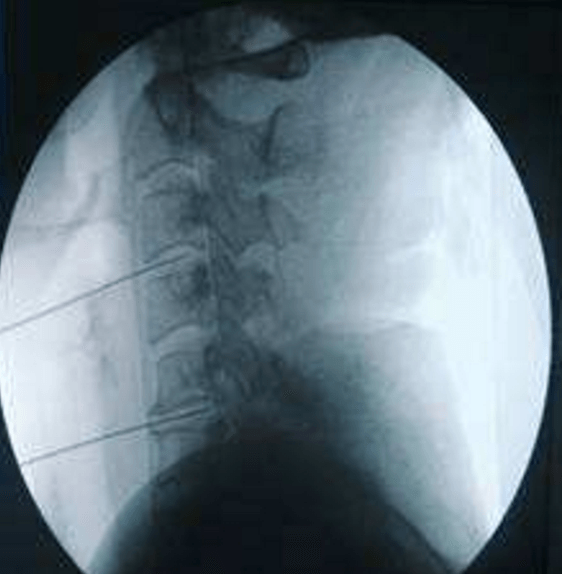

颈、腰椎间盘射频微创手术

经过多年的发展,现在的延安大学咸阳医院疼痛科在诊疗技术上已经达到一流的水平。尤其在颈、腰椎间盘突出微创治疗方面,手术量居地区前列,脊柱压缩骨折椎体成型术、颈、腰交感神经射频调控微创手术、三叉神经痛、带状疱疹后神经痛以及外周血管介入、肿瘤微创介入、内脏出血等介入治疗方面,为地区最优秀的疼痛科之一。